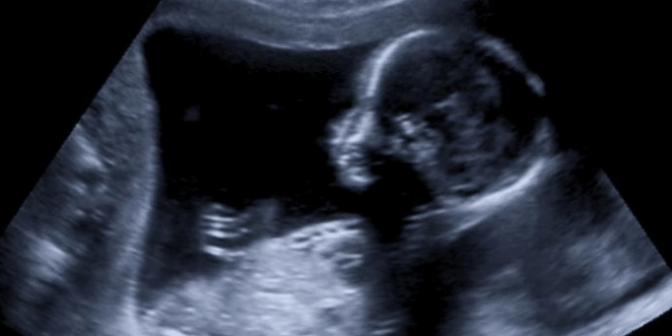

USG kehamilan atau ultrasonografi adalah teknologi yang kini sudah sangat umum di Indonesia. USG biasanya dilakukan pada ibu hamil untuk mengecek kondisi janin dalam rahim.

Berbagai macam kelainan janin dapat diketahui melalui USG ini. Ada banyak sekali manfaat dari USG kehamilan selain untuk memantai tumbuh kembang bayi sesuai usia kandungannya.

Pada trimester pertama, perkembangan janin belum terlihat jelas. Kemudian pada trimester kedua, janin mulai terlihat jelas pertumbuhannya.

Memasuki pada masa trimester ketiga, semua organ bayi mulai terbentuk sehingga dapat terlihat dengan jelas. Jenis kelainan yang bisa dideteksi melalui USG adalah ukuran bayi, jumlah jari, bentuk tangan dan tulang lainnya.